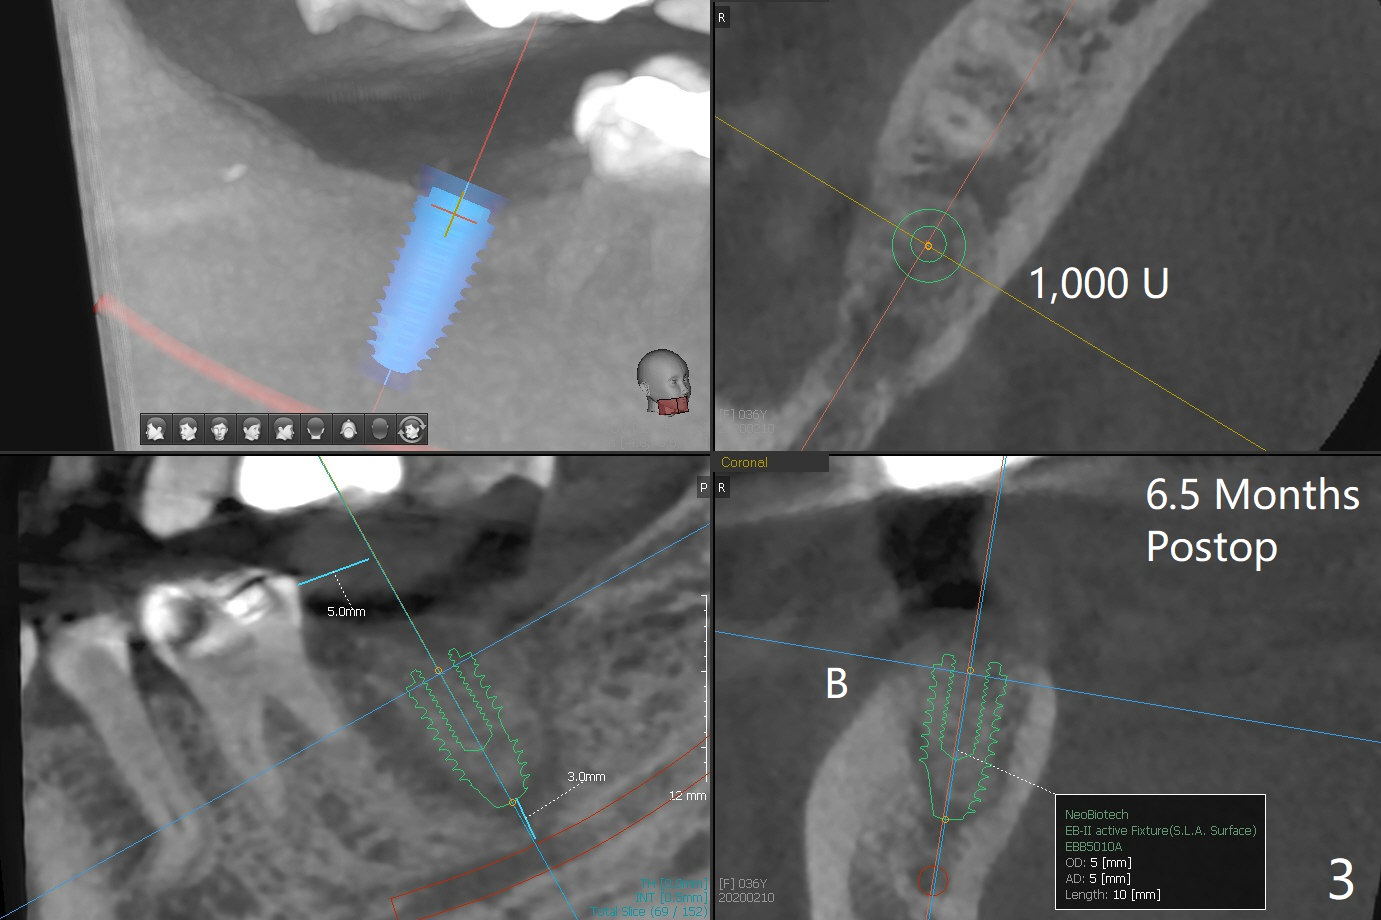

After immediate implant at #3, the tooth #31 with distal root fracture (Fig.1 *) and being close to the Inferior Alveolar Canal (red dashed line) is extracted for socket preservation (Fig.2 yellow dashed line). Although no PRF membrane is used to cover the socket, allograft is mixed with PRF liquid. A piece of 6-month membrane is used instead. The bone density is average 1000 units (Fig.3) and the ridge height is maintained 6 months postop (Fig.4). In fact the bone density of the grafted bone is low as compared to that of the native one.